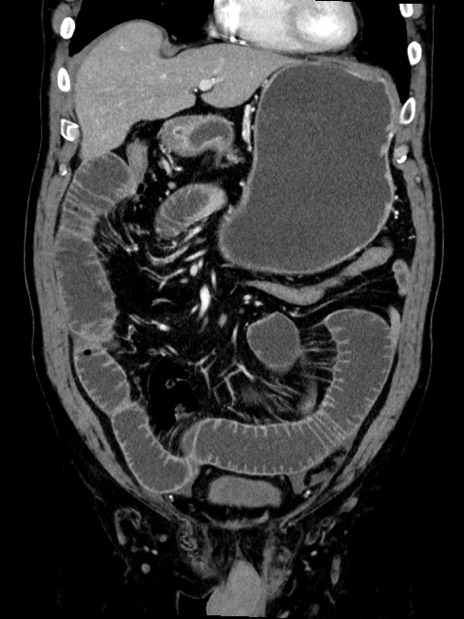

症例35(冠状断像)

【症例】70歳代 男性

【主訴】腹部膨満、嘔吐

【現病歴】昨日より腹部膨満感出現。本日増悪し、仙痛出現。嘔吐あり、受診。

【既往歴】糖尿病、胆摘後

【身体所見】BP 149/80mmHg、HR 74/min、BT 35.9℃、腹部:膨満、軟、圧痛なし。腸雑音減弱あり。上腹部正中切開瘢痕あり。

【データ】WBC 13500、CRP 1.72